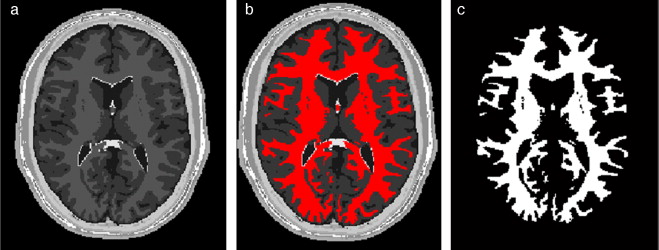

En la figura 27 se presentan los resultados obtenidos al segmentar la zona de la materia blanca con las rutinas y mencionadas. En la figura 27 .a se presenta la imagen phantom original, mostrando el corte axial número 98 del phantom . En la figura 27 .b se presenta la imagen phantom con ruido aditivo gaussiano. En la figura 27 .c es mostrada la imagen resultante luego de filtrar (b) con el filtro de difusión anisotrópica, además se observan las 5 semillas (seed points) seleccionadas de manera arbitraria sobre el área de la materia blanca. Las semillas empleadas tenían forma esférica de 2 pixels de radio, con el centro en las coordenadas X,Y,Z , las coordenadas de las semillas son: Seed1= (65,59,98), Seed2 =(112,55,98), Seed3 =(117,104,98), Seed4 =(127,137,98), Seed5 =(55,128,98). En la figura 27 .d se presenta el resultado de la segmentación (en rojo). En la figura 27 .e se presenta la zona de la materia blanca proporcionada por BrainWeb.

|

|

|

Figura 27. Materia blanca segmentada en volumen phantom . (a) Corte axial número 98 de imagen de phantom original. (b) Imagen original con ruido gaussiano agregado (c) Imagen con ruido filtrada con filtro de difusión anisotrópica. (d) Materia blanca segmentada con algoritmo Region Growing con 5 semillas esféricas. (e) Zona de la materia blanca segmentada por BrainWeb . |

Se calcularon los valores estadísticos y los respectivos porcentajes de error entre el volumen segmentado y el volumen proporcionado por BrainWeb, los resultados son presentados en la tabla 3 . Obsérvese que el porcentaje de error del número de pixels global no supera el 3,6374%, y para los descriptores estadísticos no supera el 7,1608%.